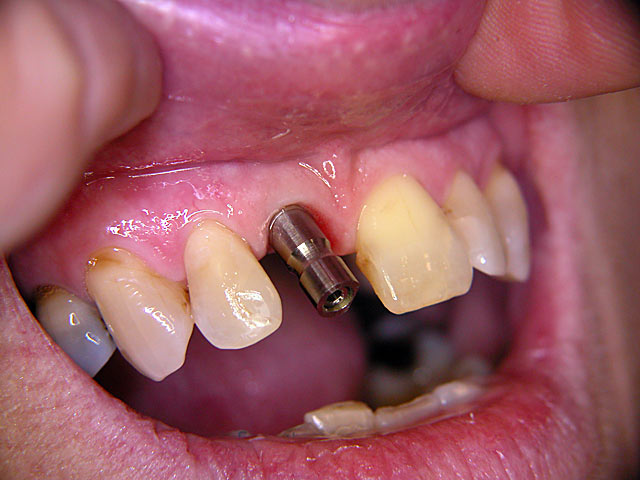

Implantation – Patientenbeispiel 2: